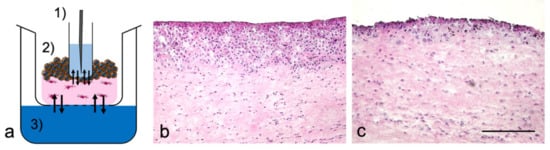

2.3. Sample Port Integration into Tumor Oral Mucosa (TOM) Models

3.1. TOM Models with Sampling Port